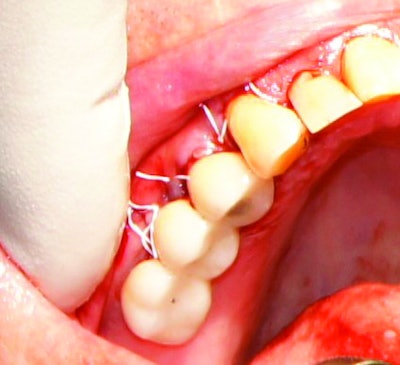

The patient recovered quickly, and no postoperative complications were observed. The one-year follow-up exam demonstrated an excellent result.

When it comes to this type of surgery, most practitioners will agree that it can be both challenging and laborious. Multiple steps have to be performed effectively or the final result could be compromised. However, using the right tool can save a significant amount of time, maximize efficiency, and ensure successful clinical outcomes.

Using a CO2 laser has many advantages. For instance, the cumbersome process of scrubbing the implant surface with gauze and then debriding the area with curettes is no longer necessary. This greatly reduces procedure time. This laser also ablates tissue quickly -- even granulation tissue in hard-to-reach crevices. Additionally, it is less invasive than traditional debridement, as the laser helps preserve healthy tooth structure.